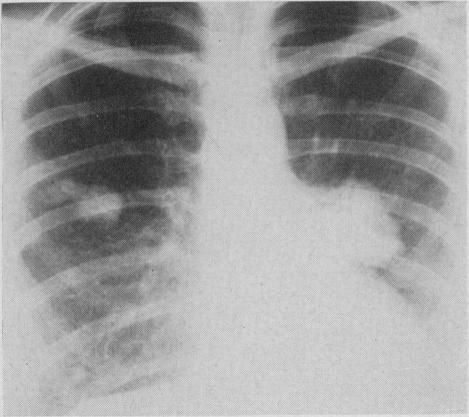

Pulmonary histoplasmosis.

Can Med Assoc J. 1959 Sep 15;81(6):486-8.